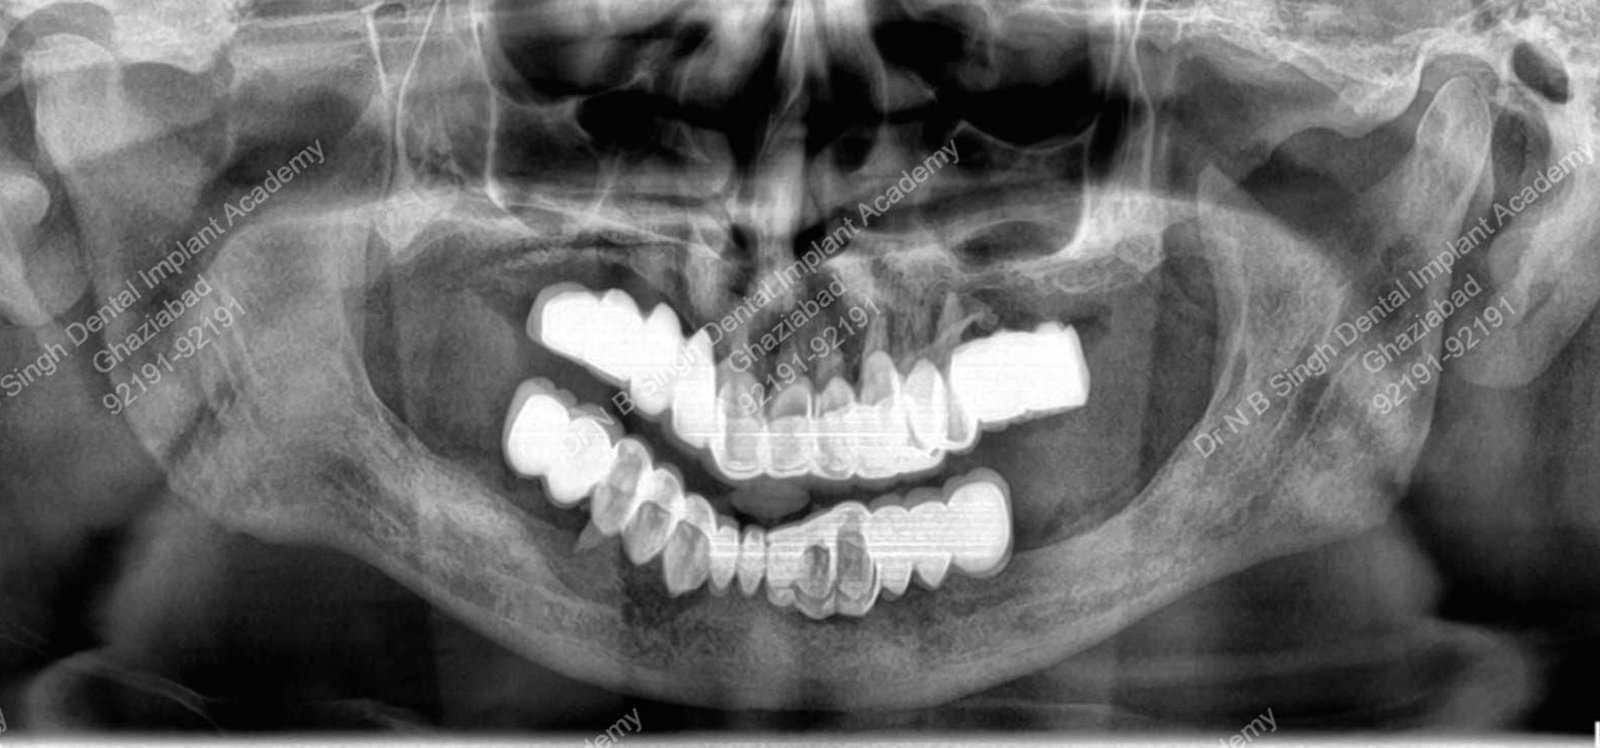

A009 opg for basal implants full mouth restoration

A009 basal implant full mouth post operative opg